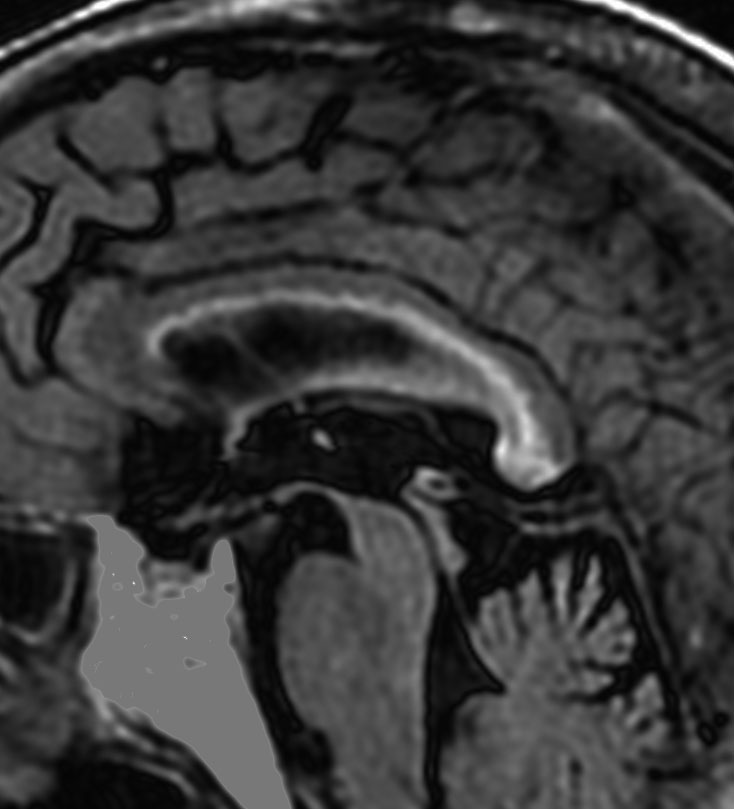

70歳女性の右後頭葉退形成性星細胞腫に対して,摘出術と54グレイ27分割の局所放射線治療をしました。右後頭葉に腫瘍摘出腔があって腫瘍再発はないのですが,治療一年後くらいから脳梁の脳室側にFLAIRで高信号の領域が広がってきました。特に星細胞系腫瘍の場合に,局所浸潤再発とまがうような所見となることもあります。ここにあげた例は典型的なもので,脳梁膨大部から膝部に至るまで脳梁内側部の白質変性が明瞭にとらえられます。